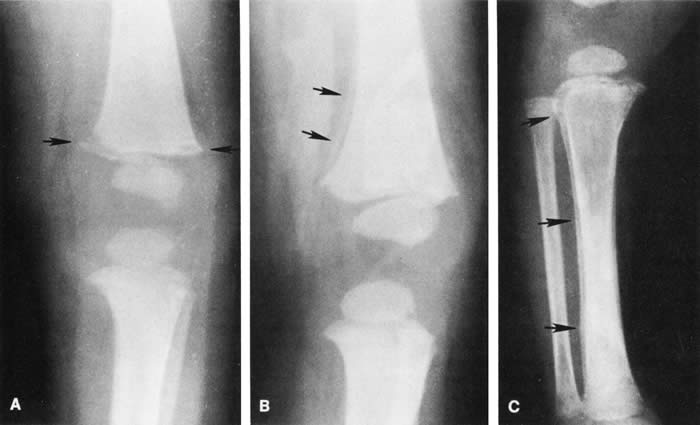

Skull fractures occur in 9% to 31% of shaken babies,23,30 with the parietal and occipital bones most affected. The characteristics of skull fractures that are highly suggestive of abuse include branching, stellate, crossing suture lines, multiple, greater than 5 mm wide, or progressively expanding fractures in a child less than 3 years of age.29 Rib fractures are the most common bone injury in SBS, and are usually posterolateral due to the perpetrator's hands grasping the child. Long bone fractures affect the tibia, forearm bones, femur, or humerus in decreasing order of prevalence. The characteristic metaphyseal fracture, which rarely occurs in young children except in the setting of abuse, results in a “corner” or “bucket handle” chip fracture at the end of the bone (Fig 9). Other injuries seen in SBS include hemorrhagic stripping of the periostium, spiral fractures, and nonsupracondylar humerus fractures—all due to shaking while the infant is held by an extremity, causing the long bones to be twisted and broken.29,30